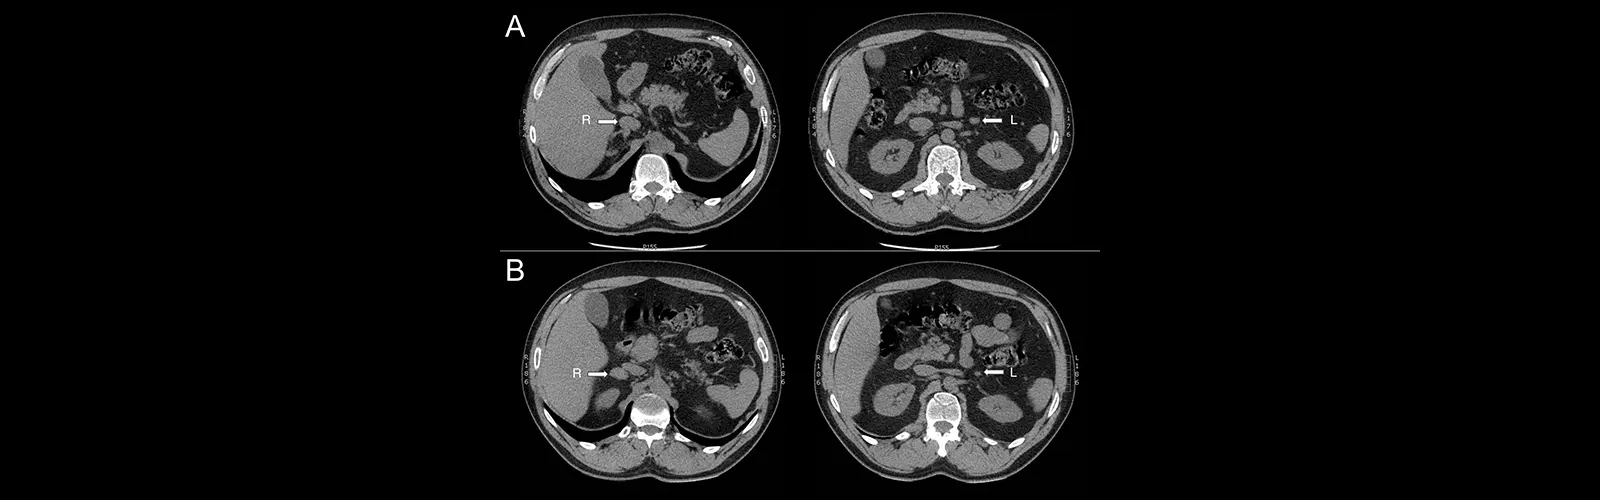

NCCT midriff is considered the gold standard imaging methodology for diagnosing kidney stones. It can identify stones as little as 1-2mm in estimate and can decide their area and number.

NCCT abdomen can be utilized to assess the seriousness of pancreatitis, a condition in which the pancreas gets to be kindled. The test can offer assistance distinguish complications such as pancreatic rot and pseudocysts.

NCCT guts can distinguish liver injuries and tumors, including hepatocellular carcinoma (HCC), the foremost common sort of liver cancer. It can too recognize other liver conditions, such as greasy liver illness and cirrhosis.